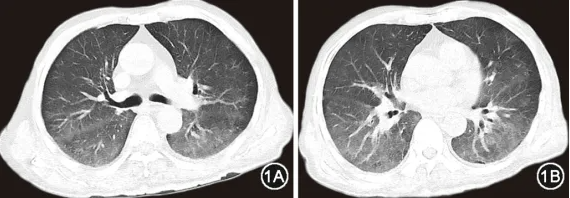

入院体检:心率106 次/min,血压157/114 mmHg(1 mmHg=0.133 kPa),外周指脉氧饱和度94%(文丘里面罩氧浓度31%支持),双肺呼吸音粗,心律齐,腹软,双下肢轻度可凹性水肿;时间定向力、计算能力差,双上肢肌力5级,下肢肌力3+级。入院后完善辅助检查:血气分析(吸入氧浓度37%):pH值为7.45,PaCO2为20 mmHg,PaO2为66 mmHg,cHCO3-为18.1 mmol/L,cLac为6.1 mmol/L;LDH为2 573 U/L;铁蛋白 1 641 ng/ml;白细胞介素(interleukin,IL)-10为134.0 ng/L。自身抗体谱:抗核抗体斑点型阳性,滴度1˸320;抗中性粒细胞胞质抗体(antineutrophil cytoplasmic antibodies,ANCA)核周型阳性,滴度1∶20。胸部CT示双肺弥漫性磨玻璃样病变,呈重力分布(图1)。

图1 患者2023年9月6日胸部CT检查可见双肺弥漫性磨玻璃影,呈向心性、重力依赖性,沿支气管、血管束分布,以双下肺为著,胸膜下较少累及